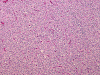

Panel A and B are low-magnification photomicrographs featuring solid sheets of isomorphous, small round to ovoid neoplastic cells with a delicate but rich vascular network. There are also intervening irregular patches of fibrillary neuropils. At high-magnification, the tumor cells appear as fairly uniform round to polygonal cells with perinuclear halo (Panel C). An island of neuropil is present in Panel D. The tumor cells are immunoreactive for synaptophysin (Panel E). The tumor cells were not immunoreactive for neurofilament proteins. At the ultrastructural level, the neoplastic cells contain numerous cell processes filled with vessicles and dense core granules (Panel F and G). Dense core granules and vescicles in high-mangification are shown in Panel H. The vesicles have structures similar to that of the synaptic vesicles, a feature of neuronal differentiation.

Histological, the tumor is composed of solid sheets of small, round to polygonal, isomorphic tumor cells with distinct cell membrane. Within the neoplastic cells is a delicate vascular network. Microcalcifications, when present, are distributed throughout the tumor. The cytoplasm is fine and amphophilic. Perinuclear halo is usually present and prominent, leading to an impression of a clear cell tumor. The summation of these features generates a “honey-comb” pattern similar to that of oligodendroglioma and clear cell ependymoma. The nuclei of neurocytoma are round, small, and contain fine and speckled chromatin. Nucleoli are indistinct. Mitotic figures are not readily seen or infrequent. Irregular and small islands of neuropils are present. Perivascular arrangement of neuropils in some areas may closely mimic the coronary perivascular fibrillary hypocellular mantles (perivascular pseudorosettes) that are considered evidence of ependymoma. The real ependymal pseudorosettes are more orderly and fibrillary. A high index of suspicion is important to avoid this trap.